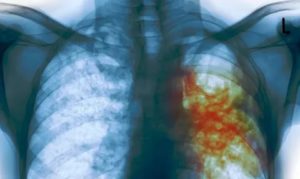

- – более точные методы. Различные формы туберкулеза выглядят по-разному на рентгенограммах (на фото). Например, при диссеминированной форме на легких имеются множественные, мелкие очаги затемнения с четкими границами, инфильтративный туберкулез затрагивает чаще всего верхние доли легких и на снимках проявляется в виде белесых затемнений с неровными краями. Очаговый туберкулез проявляется в виде затемнений диаметром до 2 сантиметров округлой формы, которые могут сливаться. Компьютерная томография обнаруживает маленькие очаги до 1 мм, позволяет рассмотреть изменения в тканях, установить форму туберкулеза, а также изучить лимфоузлы, которые не всегда заметны на рентгене.

Острый диссеминированный туберкулез